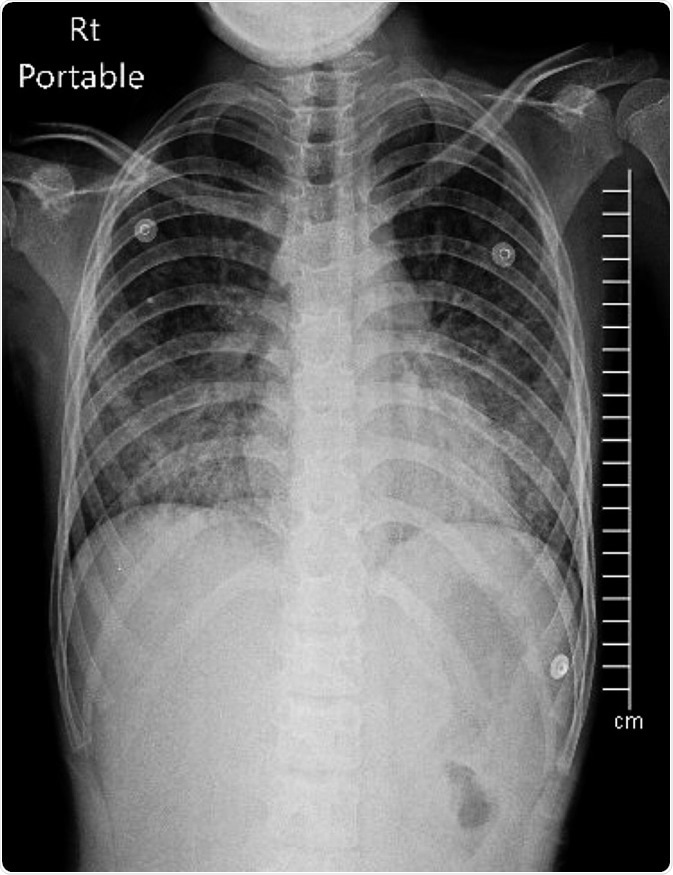

Acute respiratory distress syndrome on Chest X-ray PA upright. Image Credit: Chalie Chulapornsiri / Shutterstock

In patients with ARDS, doctors may recommend diagnostic tests to determine the severity of the condition, including a chest X-ray, sputum culture to identify the pathogen involved, arterial blood gases, and blood culture.

Oxygen levels are monitored, and the doctors will note for the presence of respiratory distress. In chest X-rays, patients with ARDS may show fluid-filled air sacs, while upon auscultation, the doctor will notice “wet” breathing sounds.